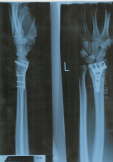

[Home] [2000] [2001] [2002] [2003] [2004] [2005] [Eggishorn] [Eishockey] [Silvester] [Furry Hütte] [Piste] [Ort] [Fackeln] [Leute] [Die Hand]